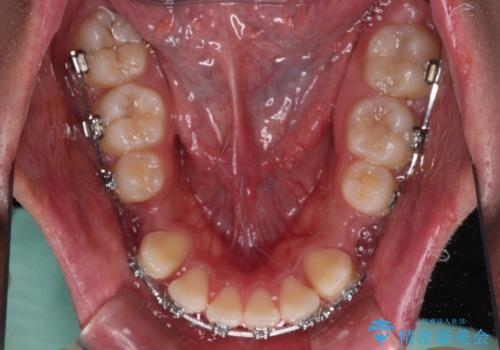

- 矯正装置

- メタルブラケット

- 前歯のデコボコと口元の突出感を気にして来院された患者様です。

上下前歯がくちばしのように突出していたため、上下左右の第一小臼歯4本を抜歯し、ワイヤー装置にて矯正治療を行うこととしました。

左上は第二小臼歯が90度捻れており、状態が良くない歯であったため、左のみ第二小臼歯を抜歯することとしました。

第二小臼歯抜歯により治療期間が長くなることを了承いただき、治療を開始しました。